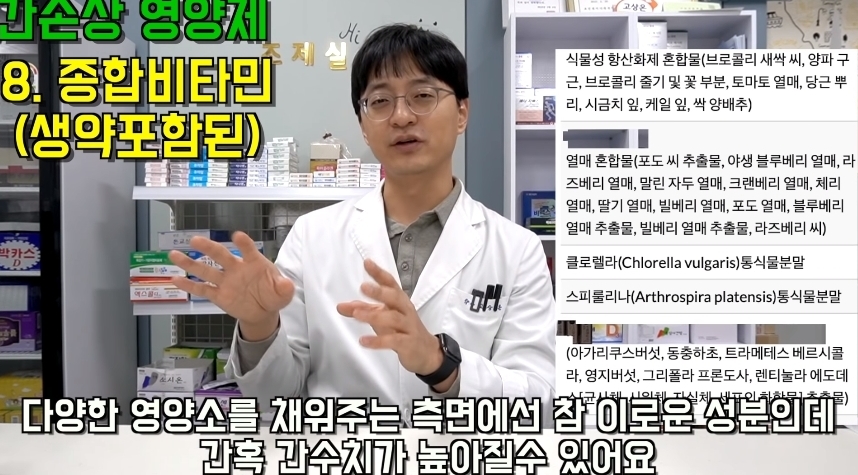

해당 게시물에는 먹으면 오히려 몸에 안좋은 영양제들이 올라왔다.